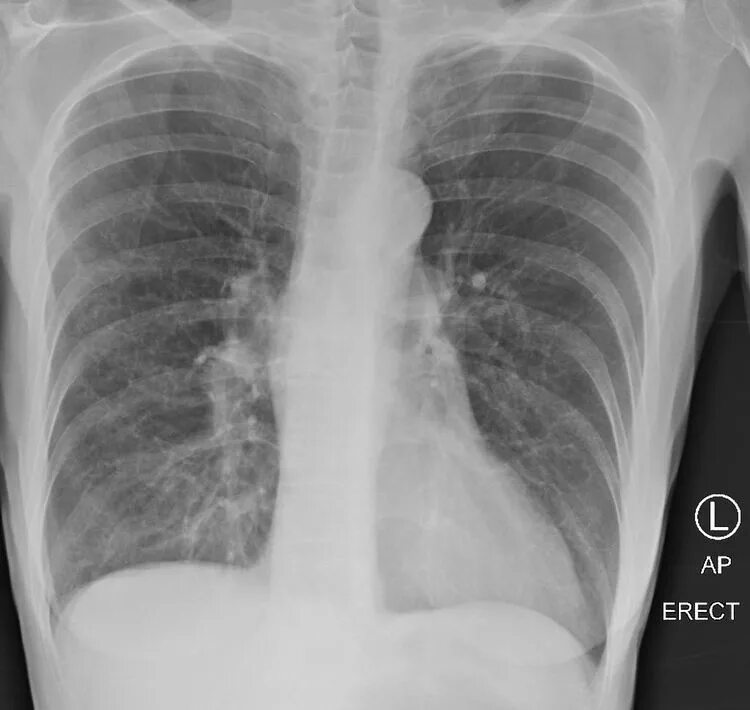

Снимок курильщика